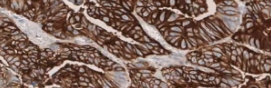

In G/GEJ tumors, CLDN18.2 status is determined by the percentage of tumor cells stained with moderate-to-strong membranous stain intensity.1

• Tissue slides with tumor cells present can demonstrate varying levels of CLDN18 membranous staining intensity, ranging from no staining to strong staining (0 to 3+)

• Two recently published phase III studies defined CLDN18.2 positivity as ≥75% of tumor cells demonstrating moderate-to-strong membranous staining3,4

Matched H&E and IHC stain of gastric tumor necrosis (10x magnification)